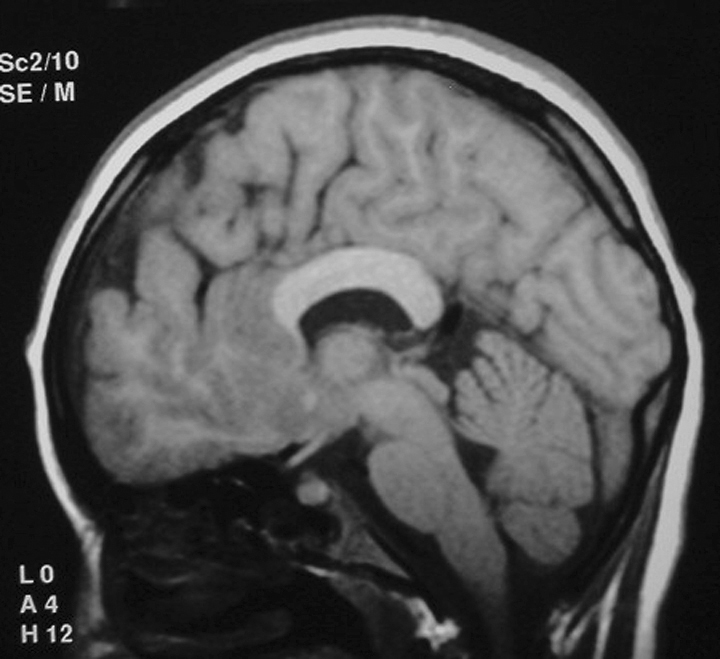

Sagittal brain MR image showing different parts of the corpus callosum …